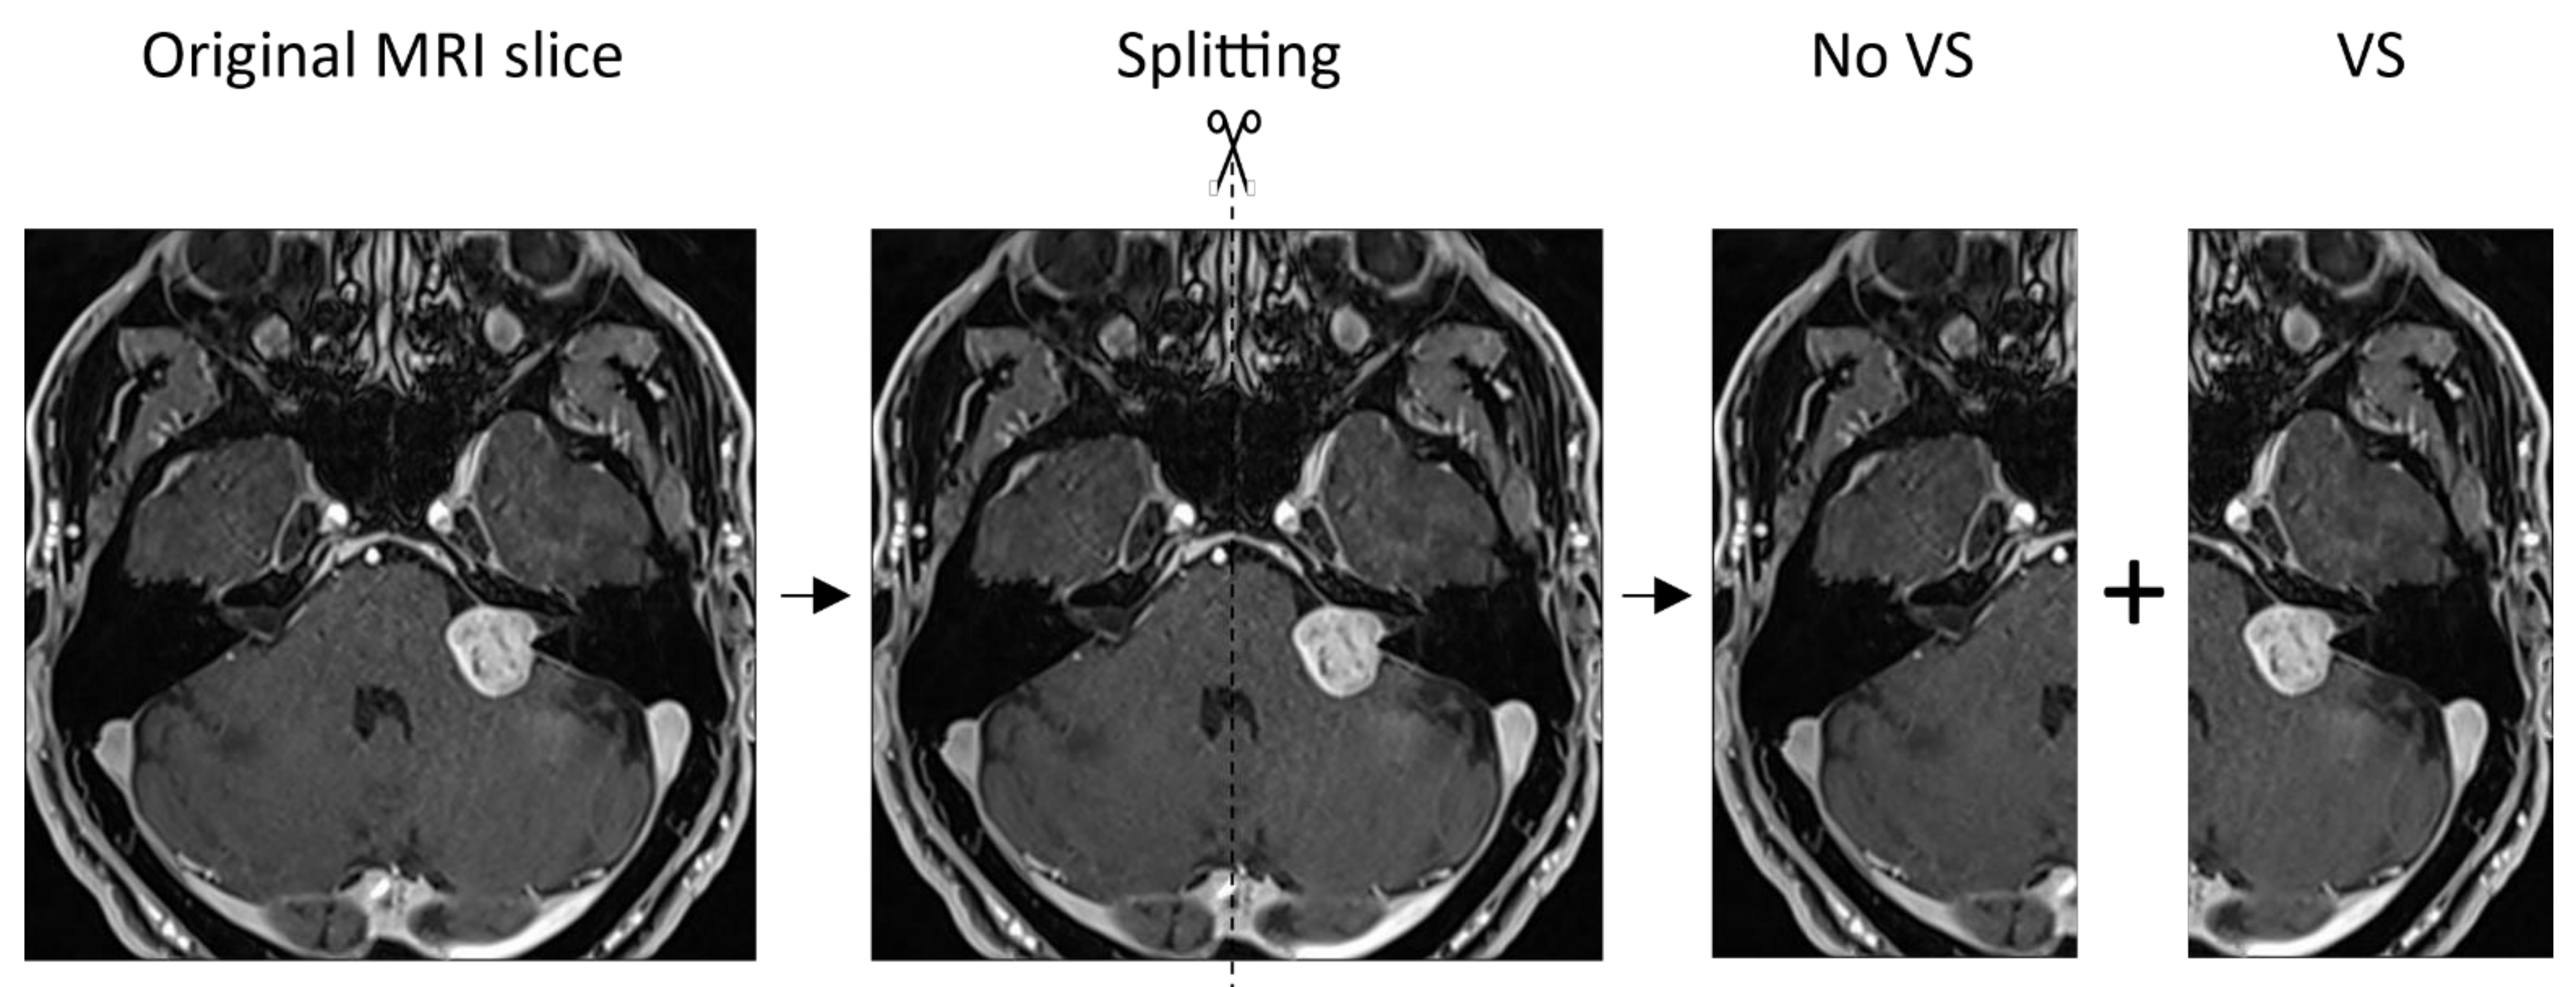

| Number of MRI slices/bisected MRI slices | 2538/5076 | 454/908 | 74/148 | 73/146 |